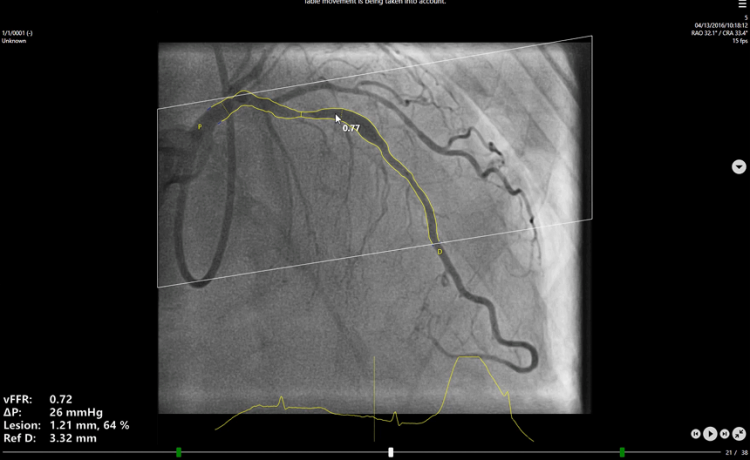

The vFFR workflow builds a 3D reconstruction of coronary artery and assesses pressuredrop, resulting in a vFFR value. Furthermore, with the 3D reconstruction anatomicalesion information is provided, like the percentage stenosis.

Functional lesion information

Pressure drops in coronary artery

vFFR value

Anatomical lesion information

Lesion diameter

Percentage stenosis

Reference diameter